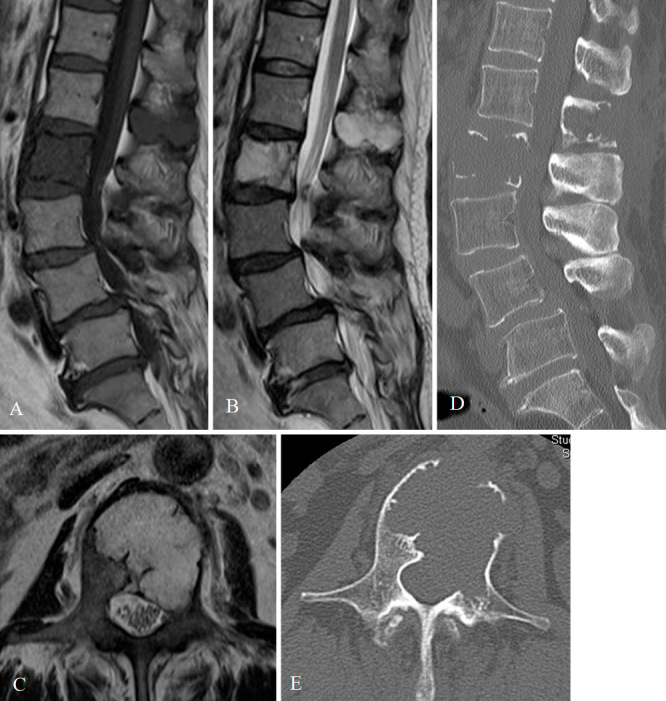

Abstract Image